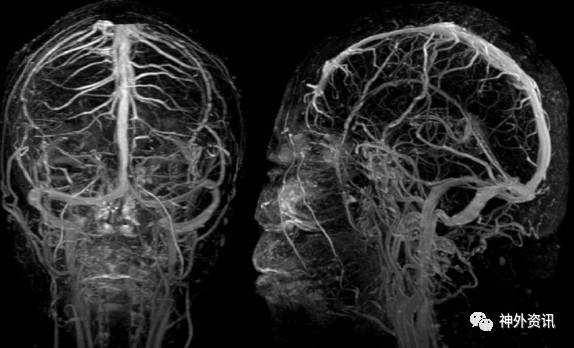

头颅CT平扫、头颅CTA及头颅MRV(图4)未见明显异常。余血化验未见明显异常。浅表淋巴结超声、胸片、心电图等相关检查均未见明显异常。

图 4. MRV 未见明显异常。